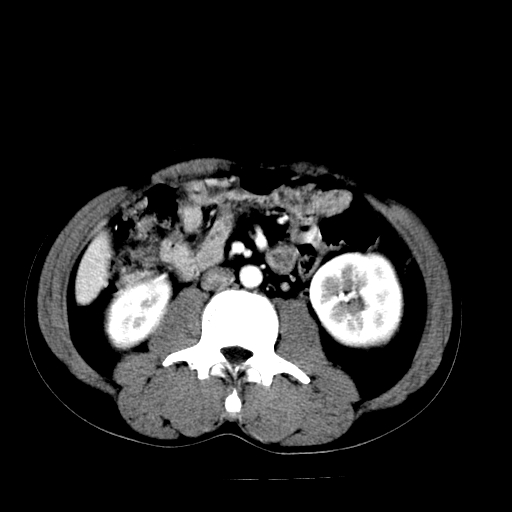

以下是引用天南地北在2007-4-30 13:36:00的发言:[br]支持慢性胰腺炎伴有假性囊肿

以下是引用andymaomao在2007-4-30 14:28:00的发言:[br]支持:1.慢性胰腺炎并假性囊肿形成可能;[br] 2.左肾形态稍增大,旋转不良。